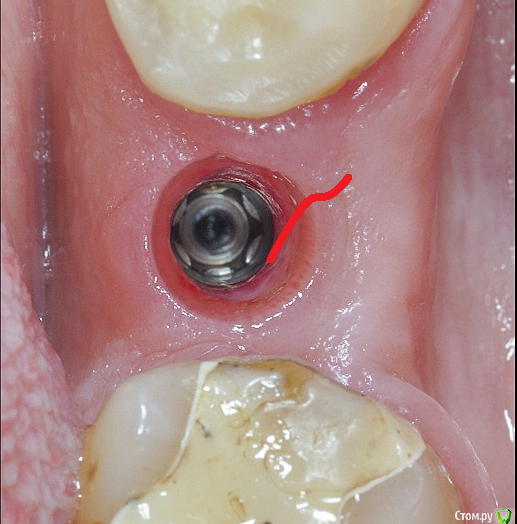

Irouil Опубликовано 13 июля, 2019 Поделиться Опубликовано 13 июля, 2019 Граница лоскута видна 11 Ссылка на комментарий

Smileee Опубликовано 15 июля, 2019 Поделиться Опубликовано 15 июля, 2019 Граница лоскута виднаКрасота!) Пробовали подшивать СДТ под полнослойный лоскут? 1 Ссылка на комментарий